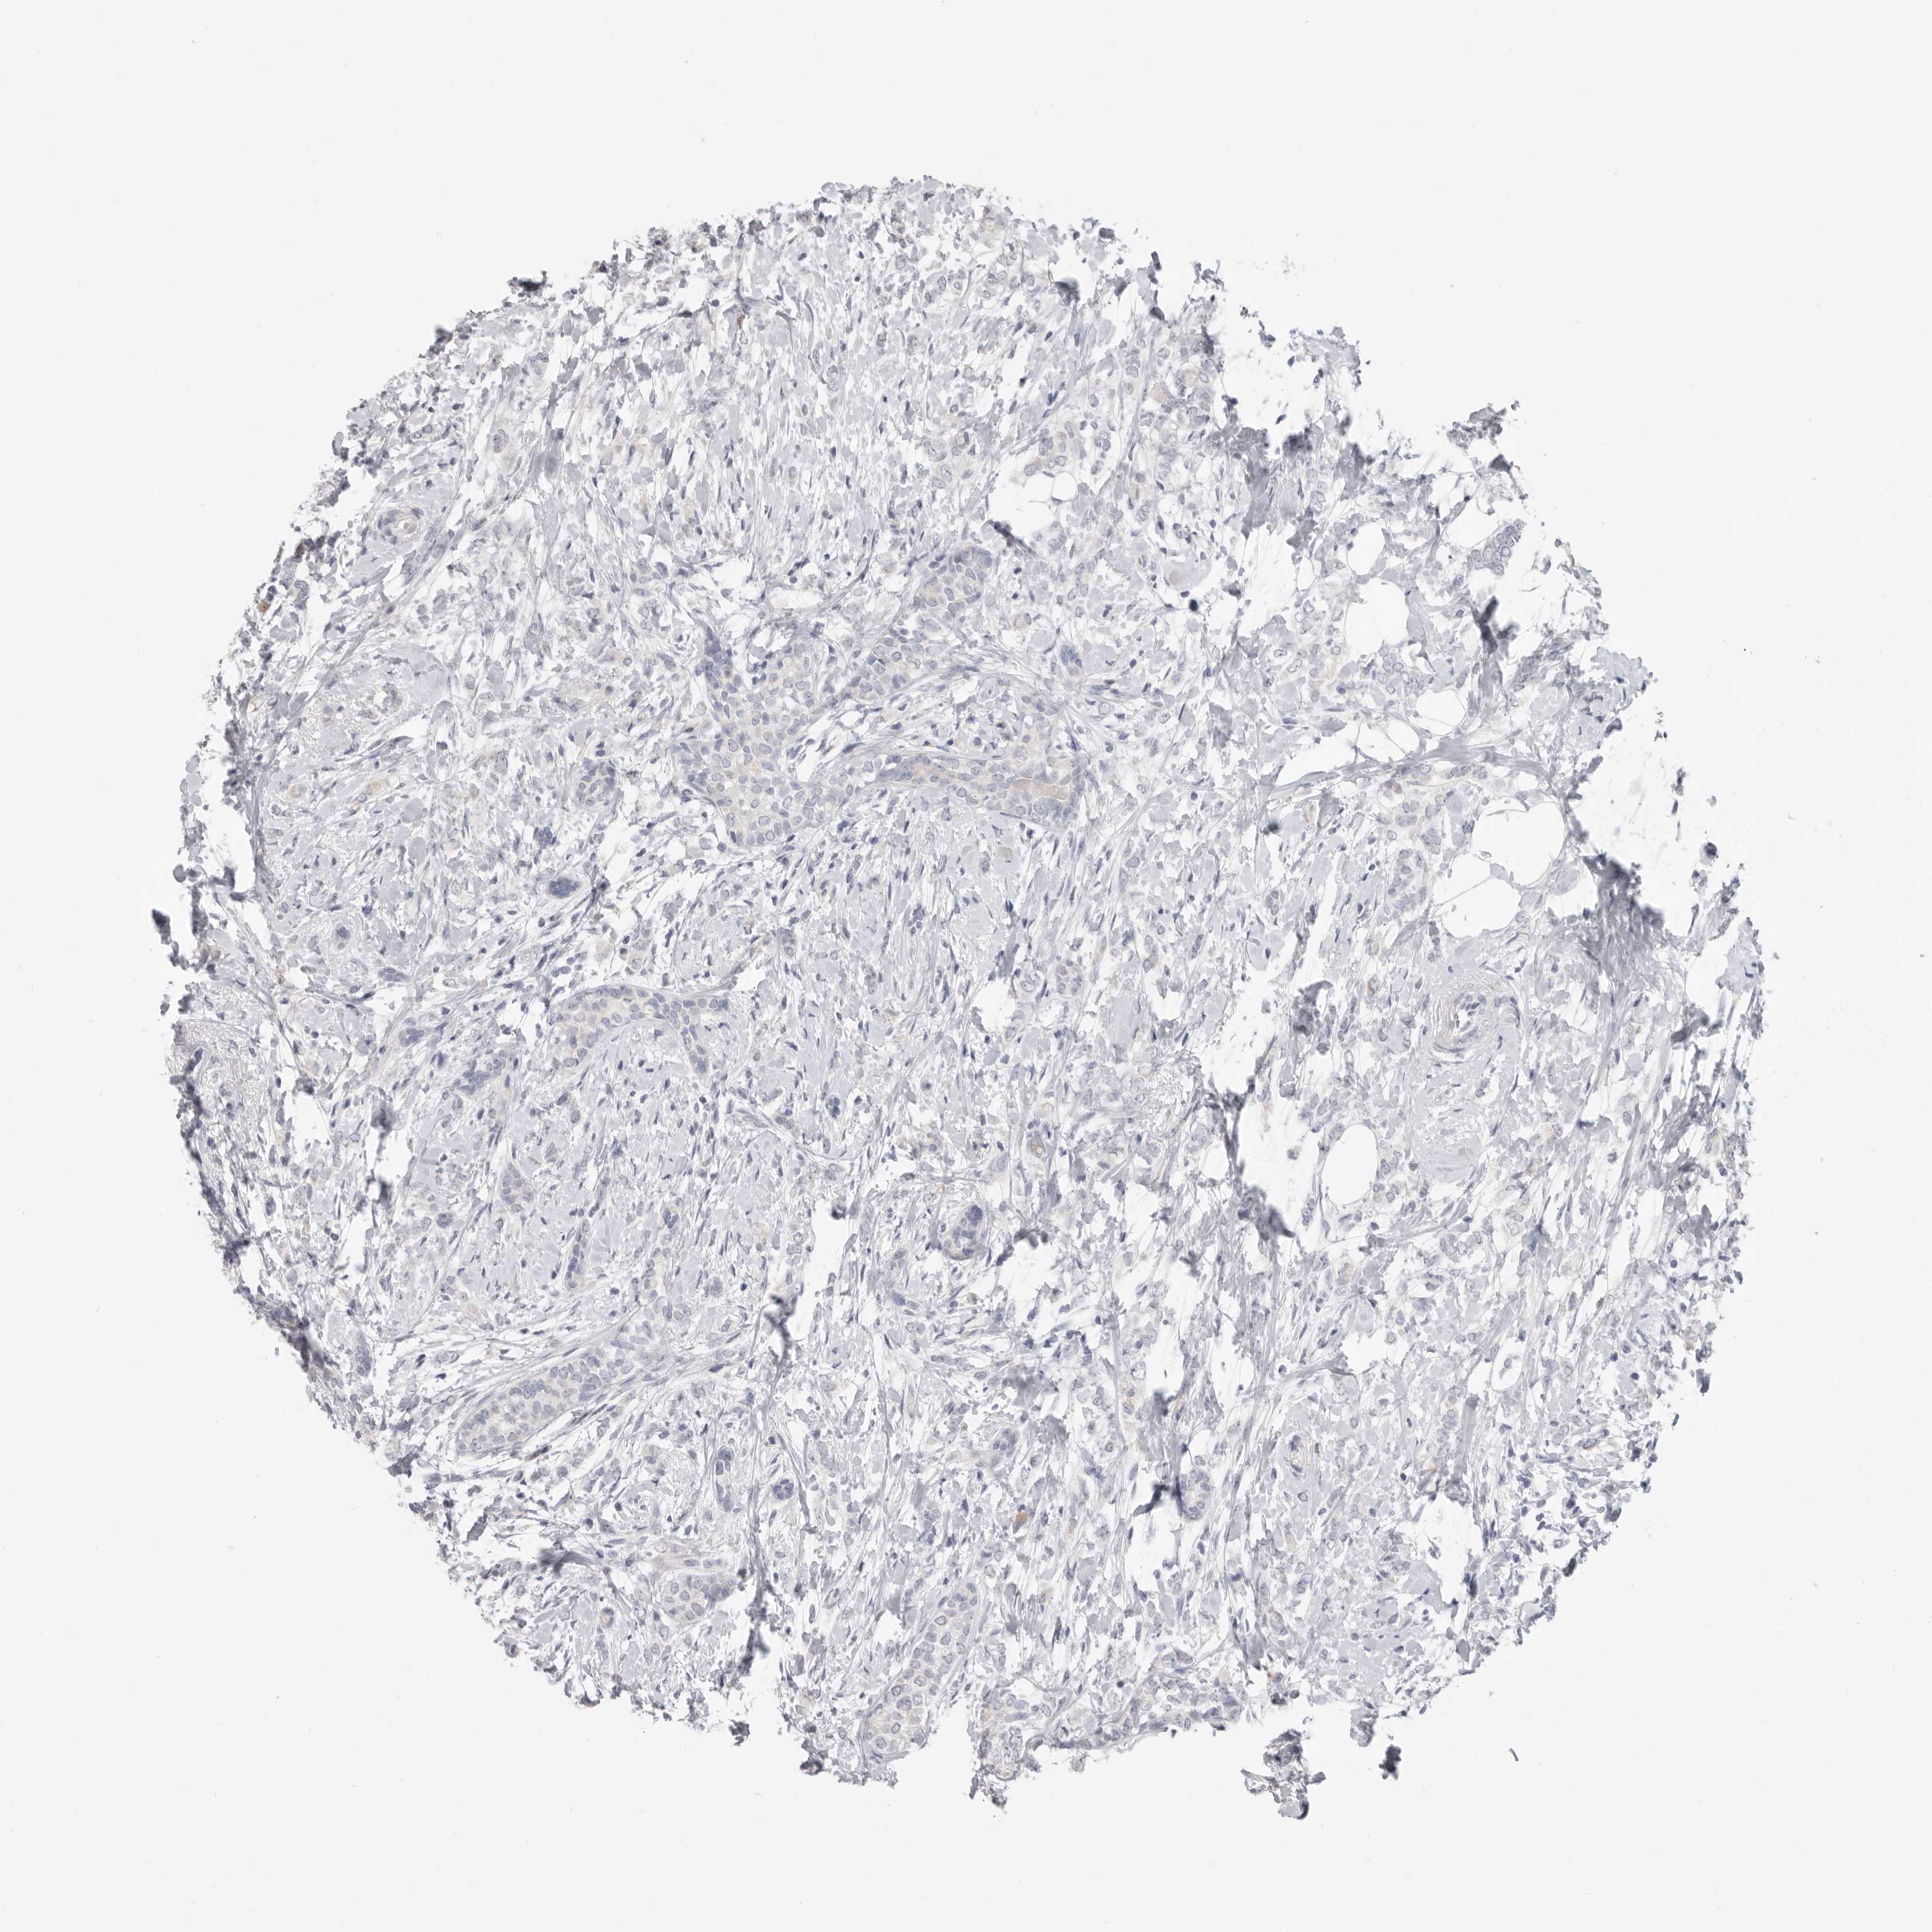

CANCER BREAST CANCER Show tissue menu

BRCA TCGA BRCA VALIDATION PROTEIN EXPRESSION

ANTIBODIES

AND

VALIDATION